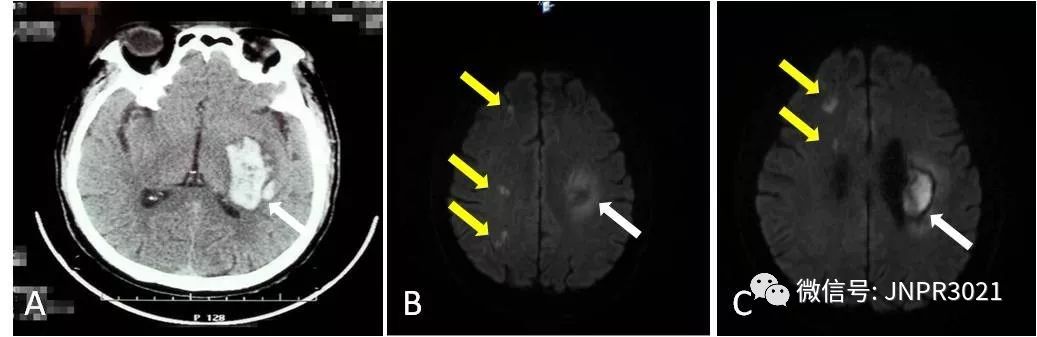

张大爷60岁,既往有高血压病史,没有规范的使用降压药物,2012年12月份前因老伴去世受刺激突发脑出血,导致右侧偏瘫。入院时头部CT显示:左侧基底节区脑出血,经积极治疗偏瘫有所恢复。因为入院期间彩超检查发现双侧颈动脉都有动脉粥样硬化斑块(不稳定斑块),低密度脂蛋白高达4.9mmol/L,发生脑梗死的风险极高,建议出院后复诊时启用预防脑梗死的药物。

入院后头颅核磁共振检查证实:除了右侧基底节区有一个陈旧性脑出血病灶外,右侧可见多发的脑梗死病灶。病人这次是真正害怕了,出院后开始服用阿司匹林和他汀类药物,定期复诊。整整7年了,张大爷既没有脑出血的再发也没有脑梗死的复发。

上图A白色箭头指示第一次住院时的脑出血病灶;图B和C为第二次住院头颅核磁共振片子,白色箭头指示陈旧性出血灶,黄色箭头指示新发的多个脑梗死病灶。